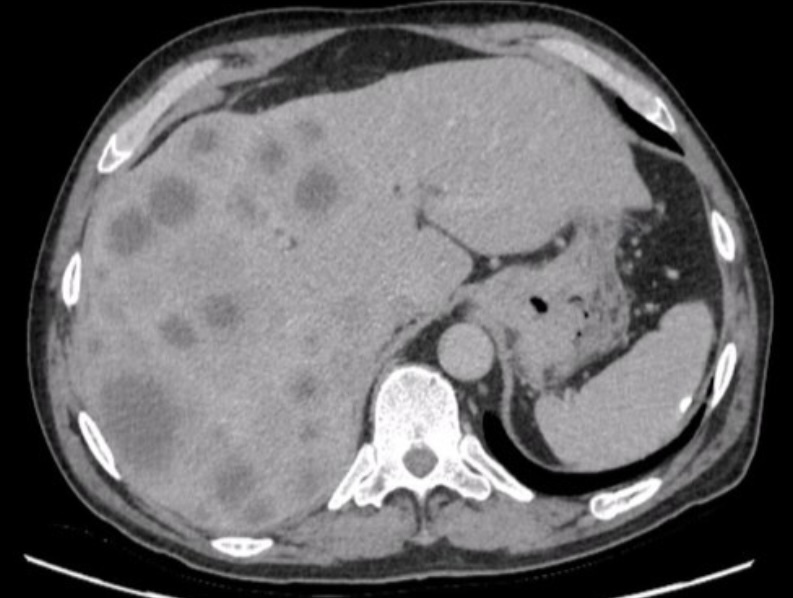

metastase hepatica na tc

TC axial aprimorada pelo contraste demonstra múltiplas lesões hepáticas hipodensas de tamanhos variados com borda periférica (aparência targetoid